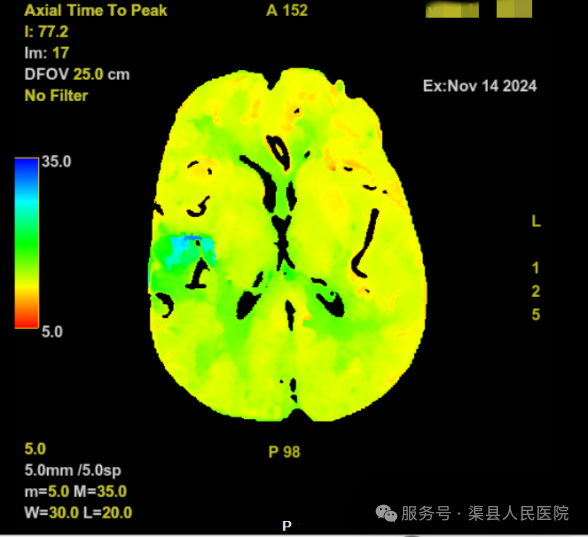

在影像联合科的全力配合下,即刻得到结果:核心梗死区:0ml,缺血半暗带:23.7ml,Mismatch比值:无穷大。结合患者的抽血结果和《中国急性缺血性卒中诊治指南》(2023版),患者具有静脉溶栓指征,立即于CT室进行溶栓治疗。

CT灌注成像(CT Perfusion,CTP)是评估脑梗死组织窗的检查,提供延长静脉溶栓、动脉取栓时间必不可少的指导证据。CTP是指在静脉注射对比剂的同时对选定层面通过连续多次同层扫描,以获得该层面每一像素的时间-密度曲线,其曲线反映的是对比剂在该器官中组织浓度的变化,间接反映组织器官灌注量的变化。

1、脑缺血性病变:灌注成像分析脑血液动力学改变,通过评价脑血流(CBF)、脑血容量(CBV)及平均通过时间(MTT)来描述早期缺血性脑卒中患者脑血流低灌注区、梗死区及缺血半暗带区,由此获得较完整的早期卒中的诊断信息。